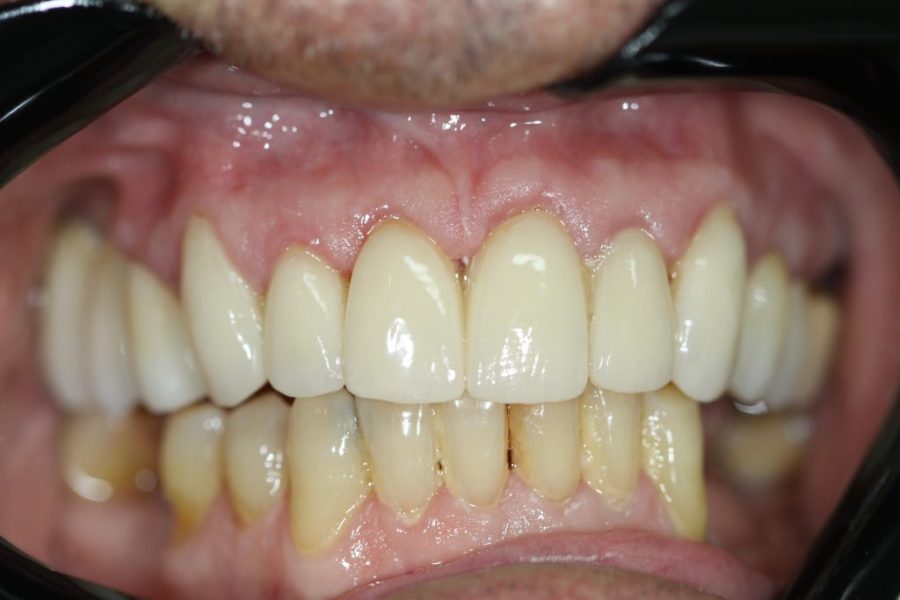

Mario’s Story: Fighting Gum Disease with Implants and Bridges

Mario came in with severe gum disease. We restored his lower teeth first, then placed four implants with a zirconium bridge for his upper teeth. Six months later, Mario’s new smile has become his favourite feature.